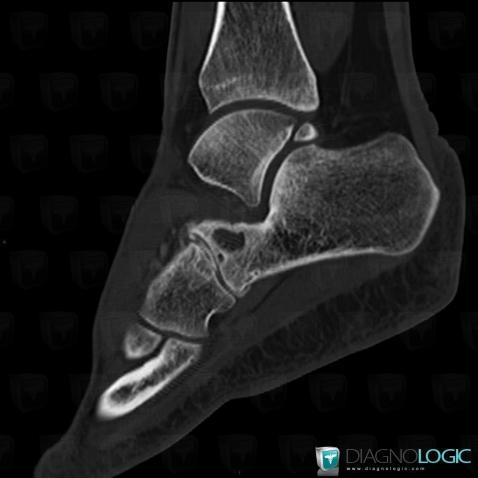

Here is the specific information in the key image above:

- Diagnosis Degenerative joint disease, Location(s) Calcaneus, with gamuts Lucent lesion in foot, Sclerotic lesion in footMid tarsal joints, with gamuts Monoarticular joint disease